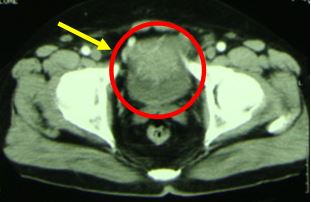

+ Bệnh nhân được tiến hành chụp cắt lớp vi tính ổ bụng để đánh giá cho thấy hình ảnh khối giảm tỷ trọng kích thước 70x90x100 mm, ranh giới rõ, bờ thùy múi, ngấm thuốc cản quang sau tiêm, trung tâm có vùng hoại tử không ngấm thuốc, khối u đè đẩy bàng quang ra sau và sang trái

Kết luận: Khối u vùng tiểu khung theo dõi lymphoma

Hình 2. Hình ảnh chụp cắt lớp vi tính ổ bụng: Khối u vùng hạ vị đè một phần vào bàng quang, đẩy bàng quang ra sau và sang trái